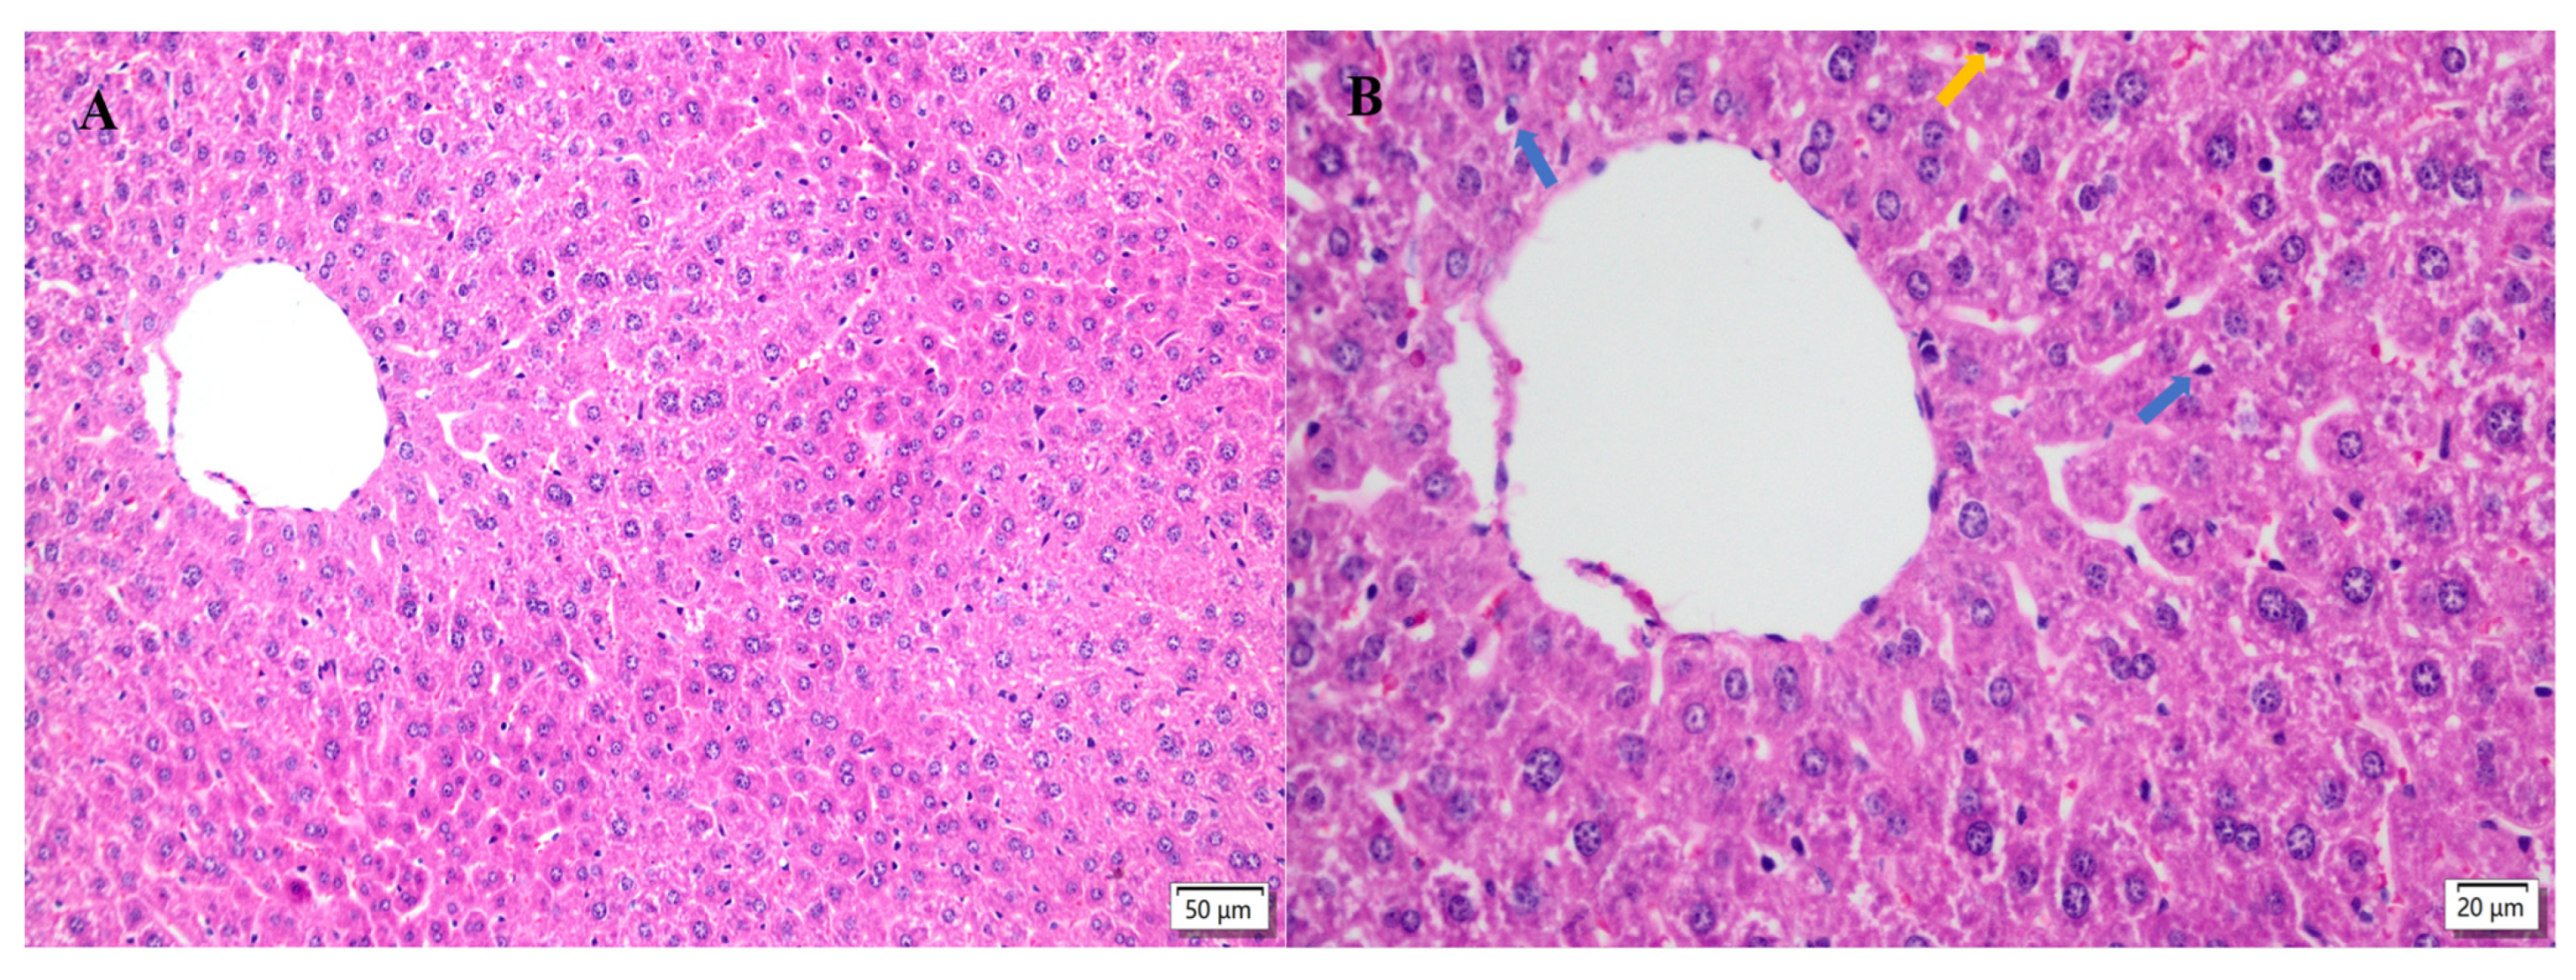

2.5. Hepatic Histopathological Changes

3.7. Hepatic Histopathological Changes